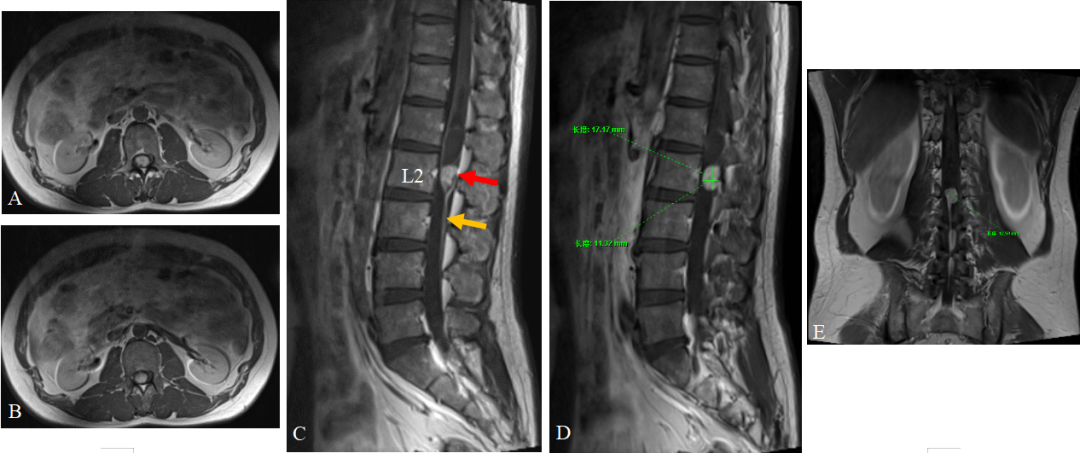

简要病史经过:患者本人诉于1年前无明显诱因出现右下肢无力跛行,偶伴有右下肢麻木症状,逐渐出现左下肢无力感。半年前患者上述症状进一步加重,并出现小便失禁,间断出现大便解不尽感。否认下肢疼痛、肿胀、虫爬感、冰凉感等。查体:下肢肤色、皮温正常,足背动脉搏动良好;神经系统查体:右下肢膝关节以下轻触觉及针刺觉减退,其余查体未见异常。辅助检查:术前MRI平扫:腰2椎体水平脊髓内可见类椭圆形实性占位(图1,红色箭头),呈混杂等T1稍长T2信号,上端脊髓囊状扩张,呈长T1长T2信号;增强序列(图2):腰2椎体水平椎管内后缘略偏右侧可见类圆形明显强化结节影,边界清晰,大小约1.73cm×1.32cm,病变与邻近硬脊膜相连,下方为终丝结构(图2,黄色箭头)。

图2. 术前MRI增强扫描。A-B轴位;C-D矢状位;E冠状位